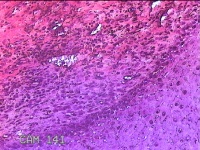

右侧食指远端结节

性别

男

年龄

47岁

临床诊断

皮下结节

一般病史

发现右侧食指3天。

标本名称

大体所见

灰白暗红色带皮肤样结节1.2x0.7x0.3cm一个,表面糜烂,切面灰白粉红色,质中。